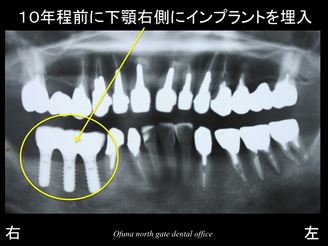

このレントゲン写真は、本当の意味での初診時ではありません。

実は、10年程前に下顎の右側の奥歯に問題があり、当医院でインプラント治療を行った方です。

下顎右側の奥にある3本のインプラントは私が10年程前にインプラント治療を行ったものです。

先程のレントゲンはインプラント治療終了時に撮影したレントゲン写真です。